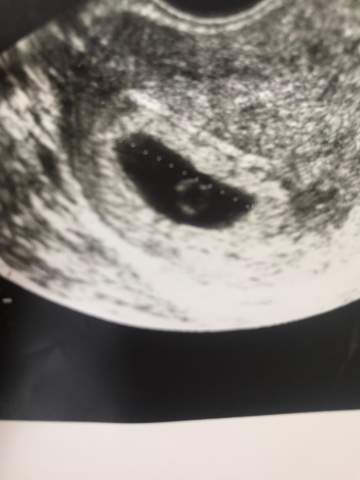

6 ssw ultraschall nur fruchthöhle Antwort 6 SSW nur leere Fruchthöhle?. Bei mir hat man bei der ersten Untersuchung auch nur eine leere Fruchthöhle gesehn Aber mein FA hat mir überglücklich zur SS gratuliert, wo ich noch total vor den Kopf gestoßen war Ich sollte dann in 2 Wochen wieder kommen und da konnte ich dann das erste Mal den Herzschlag sehen. Ich habe eine frage ich bin das zweite mal schwanger und jetzt aktuell bei 61 sprich 7 Ssw Ich hatte vergangenes Wochenende ein grosses Hämatom neben der Fruchthöhle was abgeblutet ist hörte nach 48 std vollkommen auf zu bluten Auf dem bild 55 sah man nur eine Fruchthöhle Genau wie gestern bei 60 Nur eine 9mm grosse Fruchthöhle.

SSW nur Fruchthöhle zu erkennen Beitrag #2 Zydie ich will nichts falsches sagen, jede von uns ist anders es gibt viele wunder, die geschehen, bei mir hat man schon beim 55 embryo gesehen, und beim 62 mit einem Herzschlag es gibt auch fälle wo man kein herzschlag gesehen hat und dann aber etwa später kam. Mein Arzt hatte nur ne winzig kleine Fruchthöhle gesehen ohne Inhalt Er meinte, demnach müsste ich 4/5 Woche sein 6 e später sollte ich wieder kommen Ja, 6 e später ich dahin und hatte echt Angst, daß man wieder nichts sieht Symthome für eine Schwangerschaft hatte ich weiterhin Ultraschall wurde gemacht und zack Baby mit. In der 6 SSW sieht man wirklich nicht mehr als eine Fruchthülle dein Gyn hat vollkommen recht mit seiner Aussage Nächste Woche wird man mehr sehen, wenn du Ende der 7 SSW bist (also 65 oder 66) wahrscheinlich auch den Herzschlag Nur keine Panik alles normal.

Woche und da sah man alles inkl Herz Nun wird mein Schatz am Samstag 14 Wochen alt, also mach dir keine Sorgen Ende 6 ssw nur leere fruchthöhle Hallo, Bei wem war Ende der 6 ssw auch nur eine leere fruchthöhle zu sehen?. Ich war auch in der 6 SSW bei meiner FÄ die meinte auch ja da ist nur ne Fruchthöhle zu sehen und ich solle zum nächsten Termin in 4 Wochen kommen habe das aber nur 2 Wochen ausgehalten Habe sie. Eine Woche später ist der Dottersack zu sehen Die Fruchthöhle ist jetzt ca 10 mm groß Bild 2 Wenn die Fruchthöhle 1 cm groß ist oder man sicher sein kann, dass die 6 SSW begonnen hat, sollte der Dottersack (roter Pfeil) zu sehen sein Es sind wieder nur einige e und das Kind erscheint im UltraschallBild.